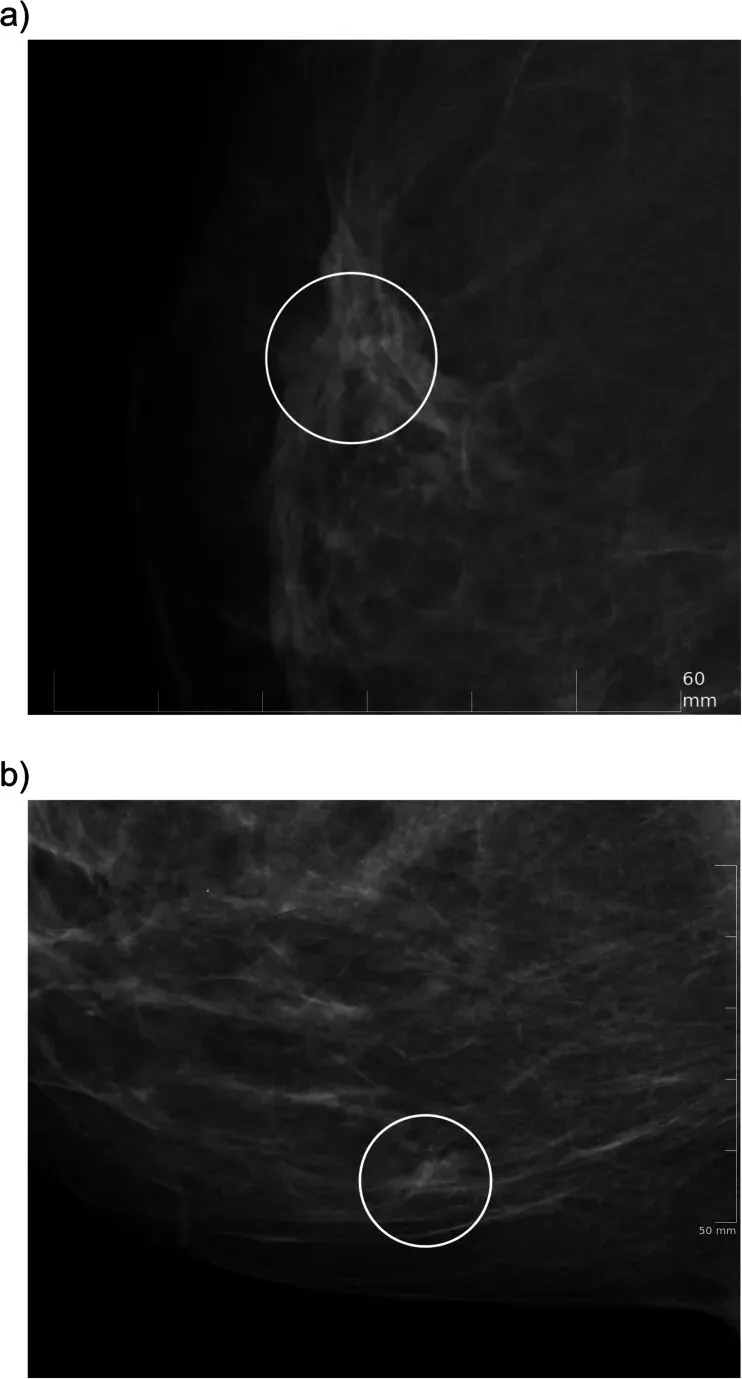

AI安全网功能成功识别了人眼漏诊的癌症病例

研究团队在论文中展示了一个具体案例,直观说明了“安全网”功能在临床实践中的关键作用。该案例中,一名接受筛查的女性其乳腺X线摄影检查最初由两名放射科医生独立审阅,两人均将其评估为阴性,对应的乳腺影像报告和数据系统(BI-RADS)分类为1类或2类。然而,集成在工作流中的AI系统基于其算法分析,将该病例判定为高度可疑,从而激活了“安全网”警报。当放射科医生在AI辅助阅片界面完成初判并准备提交阴性报告时,系统弹出了提示框,醒目地标出了图像中被AI认为可疑的区域。这促使医生重新、仔细地评估了该区域。经过再次审阅,医生改变了最初的判断,将病灶的评估等级提升至BI-RADS 4类或5类,即建议进行活检。后续的穿刺活检病理结果证实,该病灶确实为浸润性癌。这一过程清晰地表明,AI的“安全网”机制能够有效捕获那些在常规双读流程中可能被人类医生忽略的细微或早期恶性征象。该案例成为AI作为有效辅助工具,提升筛查敏感性的直接证据,避免了潜在漏诊。研究团队指出,在整个研究期间,类似这样由“安全网”触发、最终被接受并确诊为乳腺癌的案例共有204例,其中包含61例导管原位癌和142例浸润性癌,这凸显了该功能在真实世界筛查环境中的实际增量价值。